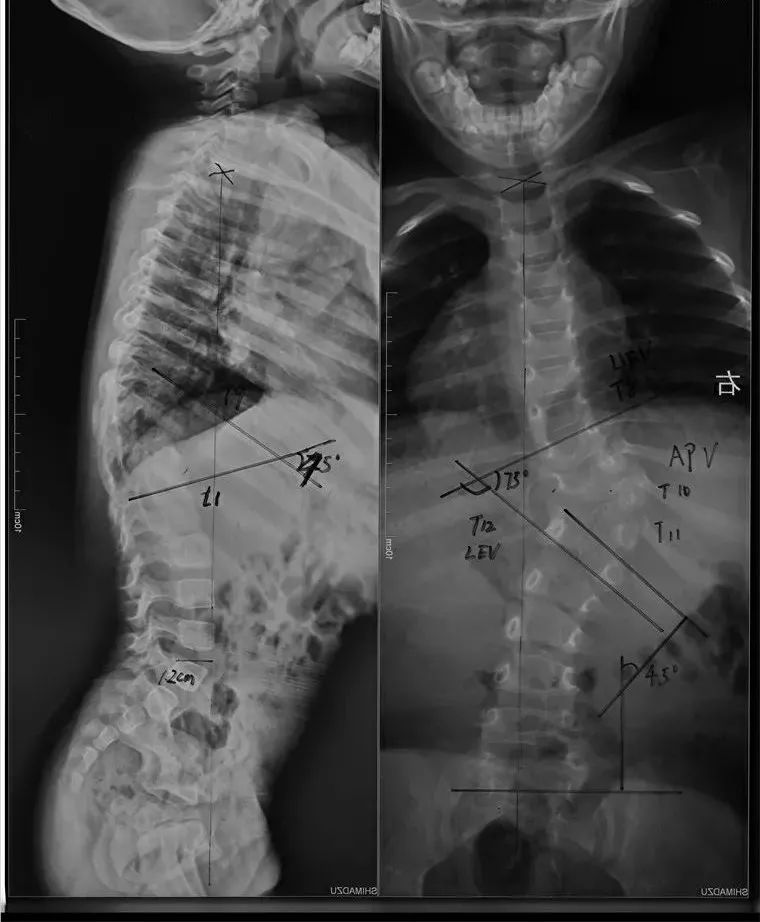

在接诊亭亭后,黄博副教授为孩子做了相关检查后发现,亭亭胸腰椎已经发生了严重的侧弯,原本正常的脊柱已变成“S”型,并且已经导致躯干的严重偏斜。黄博副教授介绍,像亭亭这样的脊柱侧弯是因为先天性的椎体发育异常造成的。有别于其他到青春期发育才发生明显形变的患者,亭亭发病非常早,通过与三个月前的X光检查对比,发现脊柱畸形明显进展,侧弯的角度已由此前的52°快速加剧到73°,如果不及时治疗,会对孩子生理和心理造成各种影响,严重的还可能导致心肺功能受损甚至死亡。

06|手术顺利完成

经过近三个小时手术,预计出血仅300ml,专家们顺利的为亭亭完成了脊柱侧弯截骨矫形手术,重新恢复了脊柱的正常序列和平衡。经过术后的X光检查,亭亭的脊柱已接近恢复到正常。